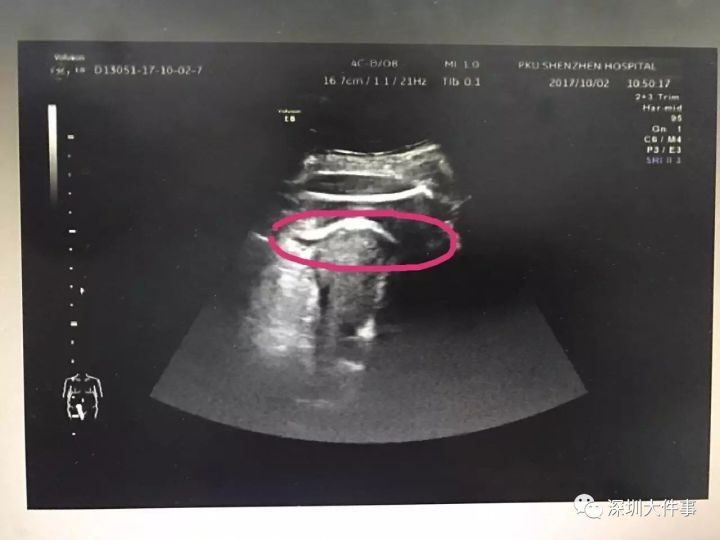

Kết quả siêu âm cho thấy chân của thai nhi đã xuyên qua thành tử cung, thò sang khoang bụng và đùi bị mắc kẹt tại thành tử cung. Nhận thấy tình hình quá nghiêm trọng, sản phụ đang đối mặt với nguy cơ bị nhiễm trùng, xuất huyết còn con dễ bị ngạt khí nên các bác sĩ đã nhanh chóng đưa chị Trương qua phòng mổ.

Vùng khoanh màu hồng là chân đứa trẻ đạp thủng tử cung.